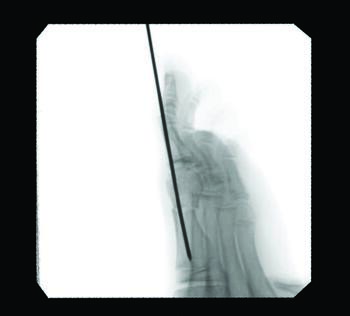

A myriad of open and minimally invasive (MIS) surgical procedures exist for this patient population, with various long-term data demonstrating outcomes, complications, and failure rates. While the literature skeptically portrays early percutaneous procedures, in my experience modern developments in technology have led to much-improved outcomes and techniques, albeit with a lack of long-term data to explain why surgeons continue to shy away from such methods. Minimizing failure rates and increasing patient satisfaction of hallux valgus correction is an important objective of surgeons continuing to improve on traditional methods. The ability of MIS to allow early mobilization by utilizing the same AO principles of traditional methods and the ease of reproducible triplanar correction continues to be a motivation, in my observation, to advance this newer approach and increase its utilization in the podiatric surgical field.

Documentation of surgical correction of hallux valgus first occurred in the early 1800s, with the earliest reports of percutaneous correction in the 1940s. Podiatric physicians experienced surgical restrictions at this time, and MIS provided an avenue for circumvention. Complications arose due to a lack of supportive means, and these outcomes led to an abrupt return to open procedures. The 1960s provided power equipment development and intraoperative fluoroscopy, which significantly improved outcomes of both open and percutaneous procedures. With the arrival of these modern tools, surgeons began to revisit the utilization of percutaneous procedures towards the end of the millennia. A subcapital osteotomy technique reported by Bosch, and “Simple, Effective, Rapid, Inexpensive,” modified by Giannini in the early 2000s, implemented a modern look at MIS hallux valgus procedures.8,9 Most recently, a guide to the percutaneous bunionectomy written by Siddiqui in 2014, and MIS radiographic outcomes in 2016, provided another available tool to surgeons, which decreased the complication rates and expanded the confidence in utilization of MIS bunion correction universally.10

Although minimally invasive hallux valgus surgery is a more modern technique, especially for the pediatric population, it still relies, in my experience, on AO principles of fracture fixation, including anatomic reduction in the first intermetatarsal and hallux abductus angles, stable fixation, preservation of blood supply, and early active mobilization. I find the percutaneous approach allows the reduction of a wide range of mild to severe radiographic angles and preservation of blood supply. In a study of minimally invasive bunion procedures, surgeons achieved up to a 12.5 degree correction of the first intermetatarsal angle and reported a 5.3 percent reoperation rate. The study was from a surgeon’s first 94 MICA procedures, and the author challenged the previously reported steep learning curve, citing low complication rates and ease of reproducibility.13

One can allow early mobilization by immediate weight-bearing in the postoperative course, most notably providing a decrease in adhesions and consequent stiffness of the joint. Another advantage includes multiple viable fixation options, including splintage with a Steinmann pin through external fixation. Many long-term risks of internal fixation include foreign body reaction, growth disturbance, chronic infection, corrosion, implant migration, and potential interference in orthopedic treatment later in life.14 Schmittenbecher and coworkers described risks of implant removal in children with various fixation options, concluding that each patient’s treatment selection must weigh the benefits and risks.14 Steinmann pin fixation may, in my experience, alleviate these risks, removing it around four weeks postoperatively.

As we all know, in stage two of fracture healing, the bone will form a fibrocartilaginous callus; this internal callus houses new blood vessels in the newly formed spongy trabeculae. Therefore, at four-week postoperative radiographs, one may not appreciate a bone bridge across the osteotomy site. As long as an intracapsular osteotomy took place through a minimal approach, I find the capital fragment should stay inherently stable. In my experience, the osteotomy site will form a robust bone bridge through mechanotransduction.